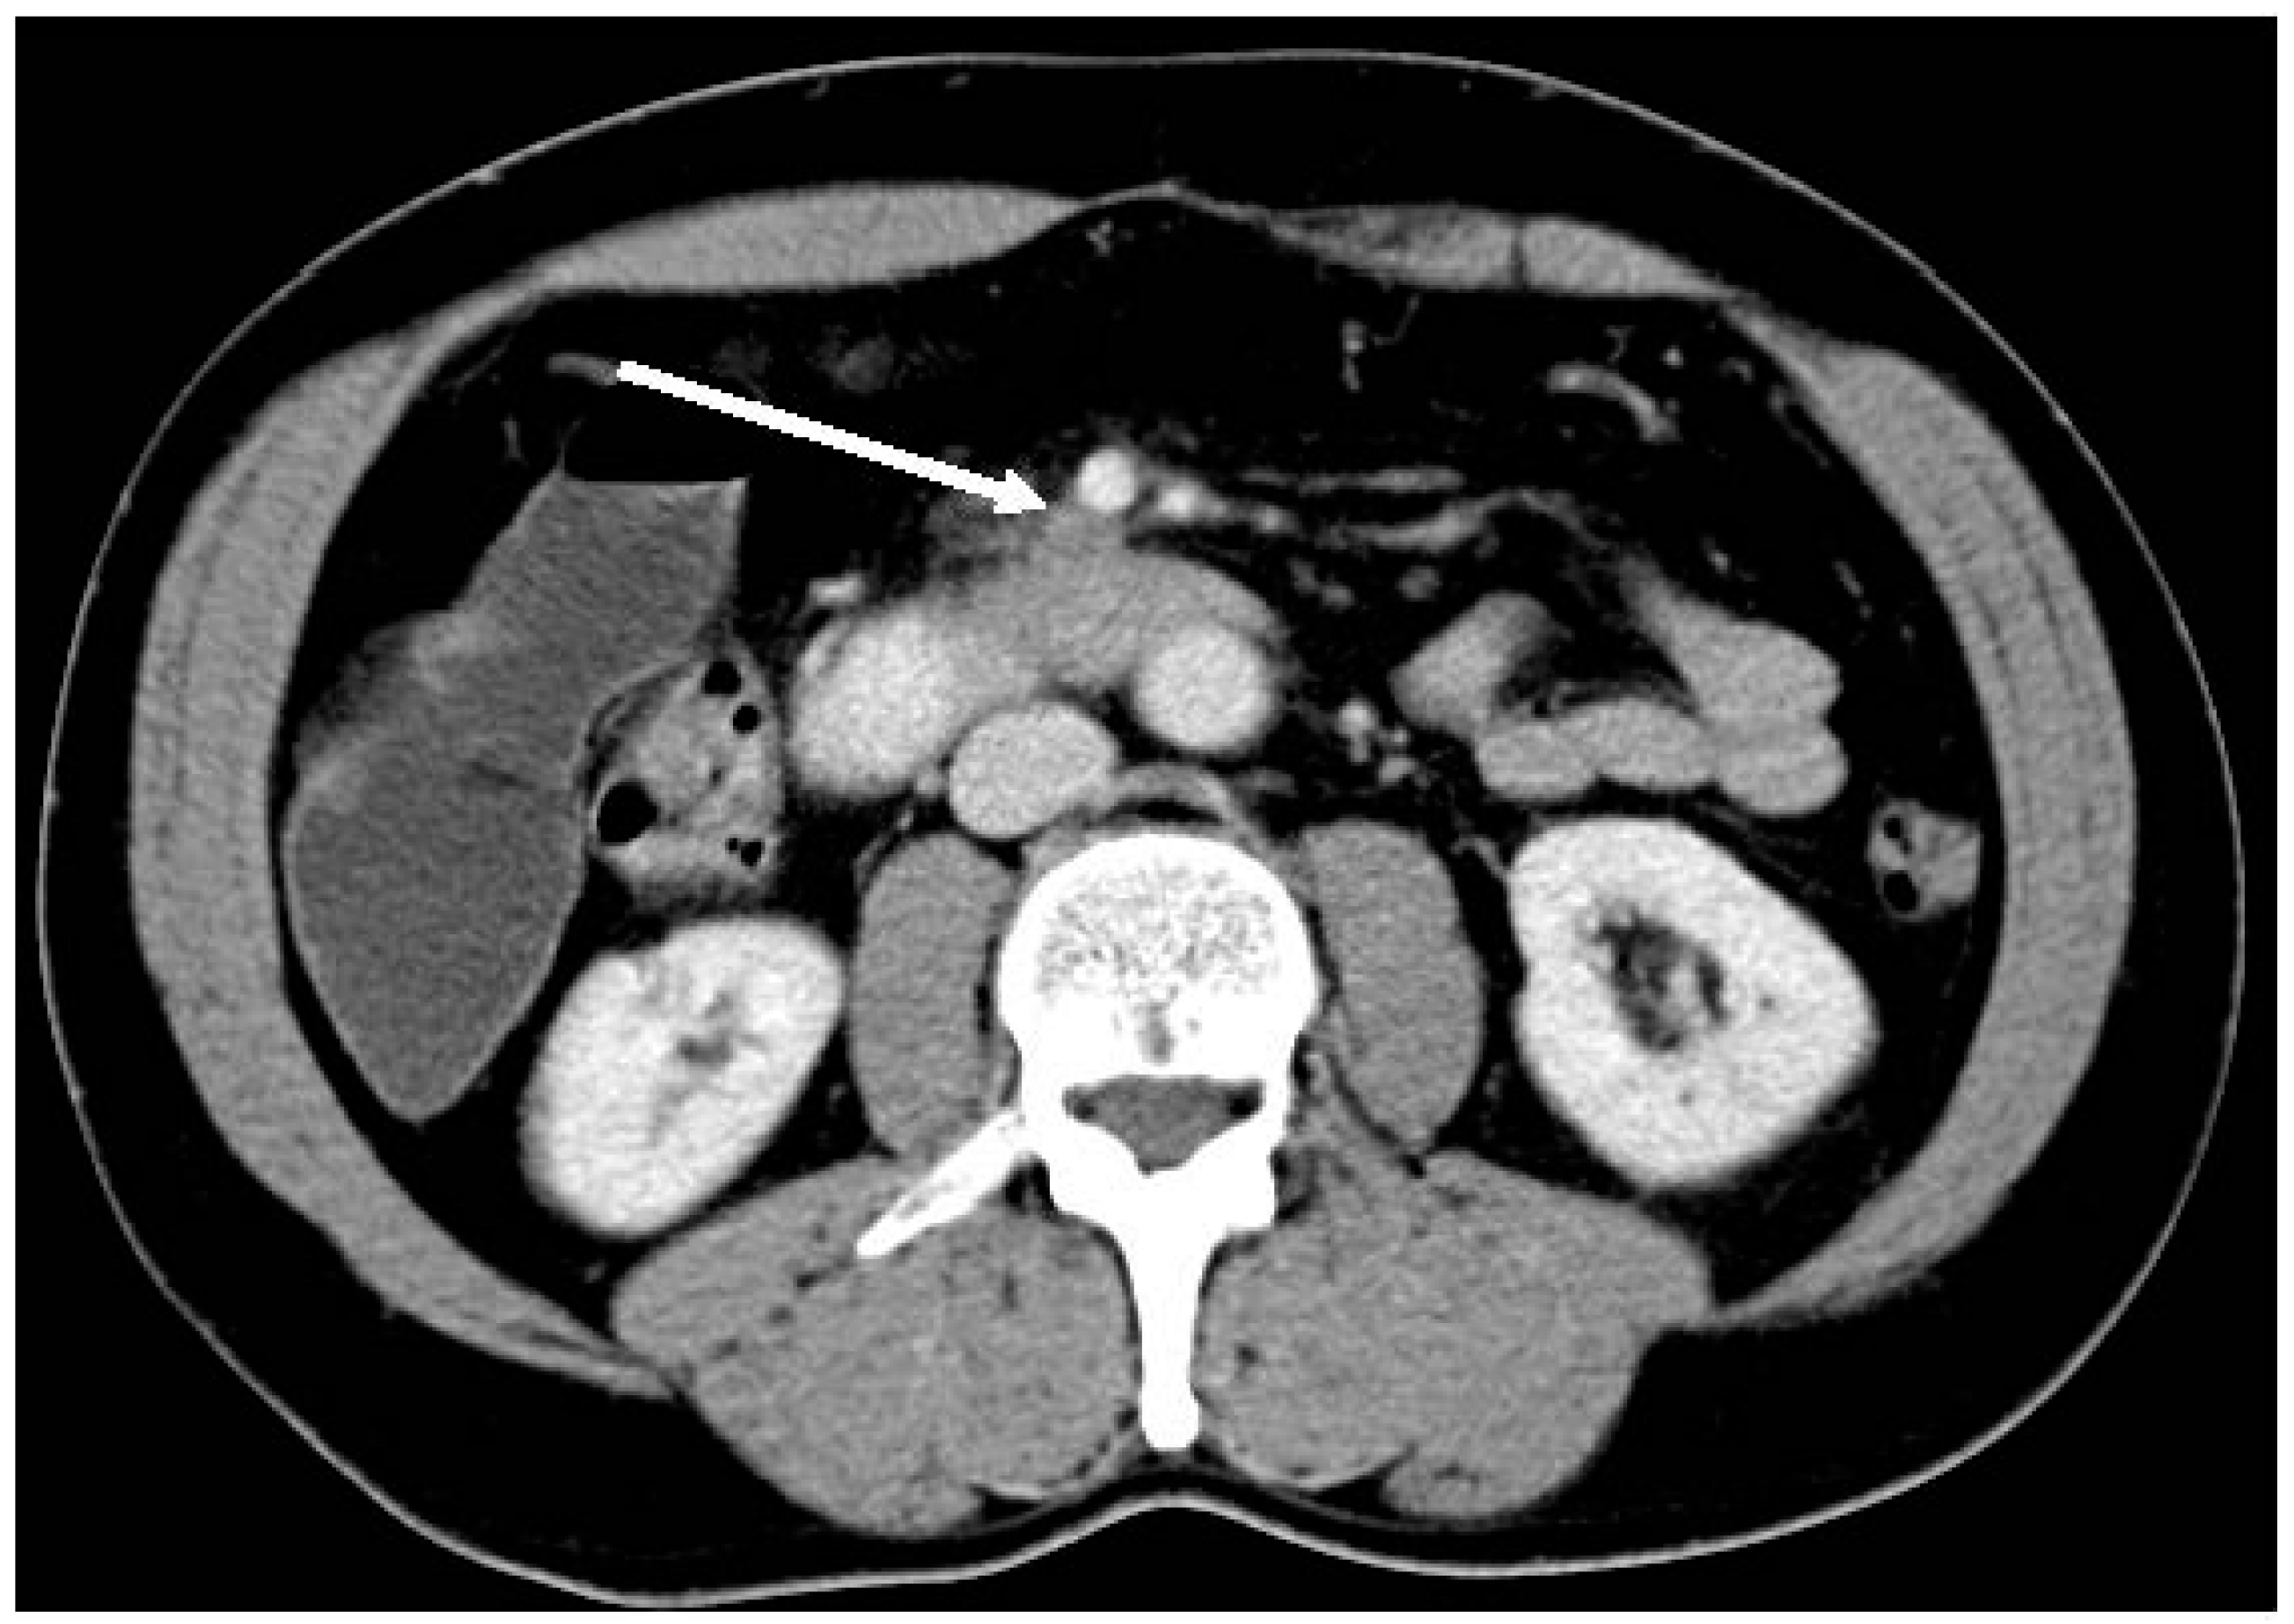

2. Definition of Resectability